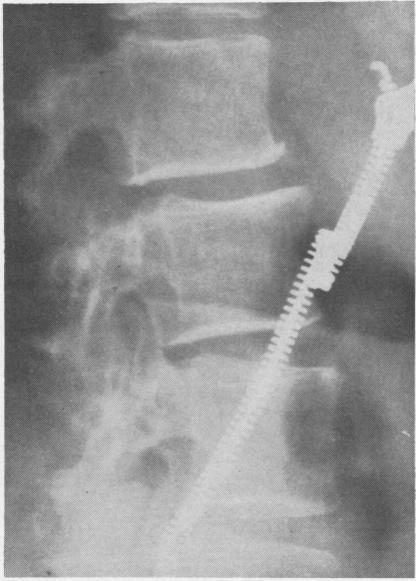

RHEUMATOID ARTHRITIS OF THE LUMBAR SPINE.

Ann Rheum Dis. 1964 May;23(3):205-17. doi: 10.1136/ard.23.3.205.